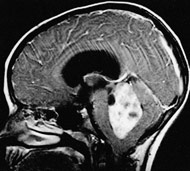

Процедуры визуализации. Магнитно-резонансная томография (МРТ) обычно применяется для постановки диагноза при опухолях головного мозга. Во время МРТ используются магнитные поля и радиоволны, которые генерируют изображение головного мозга. В некоторых случаях в вену руки вводится контрастное вещество до начала проведения МРТ. Несколько специальных изображений МРТ могут помочь врачу оценить ситуацию и назначить план лечения, включая проведение функциональной МРТ, перфузионной МРТ и магнитно-резонансной спектроскопии.

Операция

Если опухоль головного мозга расположена в месте, доступном для проведения операции, хирург постарается удалить всю опухоль настолько, насколько это возможно. В некоторых случаях опухоли являются небольшими по размеру и их можно легко отделить от окружающей головной мозг ткани, что делает операцию по полному удалению опухоли оправданной. В других случаях опухоли расположены около чувствительных зон в головном мозге, что делает операцию рискованной. В таких случаях врач может попытаться удалить опухоль настолько, насколько это безопасно. Удаление даже части опухоли головного мозга может помочь ослабить признаки и симптомы заболевания. В некоторых случаях берется лишь небольшая биопсия для подтверждения диагноза.